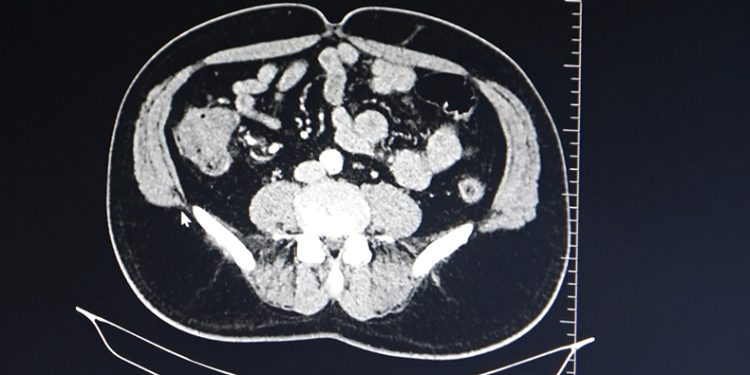

Bunun dışında ailesel yani genetik olarak kanser vakaları bulunmakta olduğunu aktaran Dr. Öner, “Aile bireylerinde kolon kanseri teşhisi konulan hastalarda, aile bireyinin tanı konulduğu yaştan itibaren 10 sene geriye gidilerek hastanın tarama grubuna girmeleri gerekmektedir. Kolon kanseri şikayetleri karın şişliği, büyük abdesti rahat yapamama, büyük abdest yerinde kanama gibi şikayetlerdir. Kolon kanserine erken tanı koyulması halinde şifa ile sonuçlanabilecek küratif olarak sonuçlanmaktadır. İleri evrede kolon kanseri alan hastalarda ise medikal onkoloji takibine girip, kemoradyoterapi işlemlerine maruziyetleri olabilmektedir” diye konuştu.

Kolon kanseri hastalarının ameliyatla kurtulabileceğini ve 40 yaşından sonra kontrollerin aksatılmamasının önemli olduğunu vurgulayan Dr. Öner, “Kolon kanserinin oluşmaması için özellikle hareketsiz yaşamdan hareketli yaşama dönülmesi, sebze ve meyvenin sık tüketilmesi, etli ve yağlı yemeklerin en fazla haftada 1-2 defa tüketilmesi gerekmektedir. Kolon kanseri ameliyatlarında ise kitlenin tuttuğu alanı besleyen ana damarlarla beraber alındığı zaman hastalar şifa buluyor. Dünyada kolon kanseri tarama yaş grupları olarak 40 yaşından itibaren yılda bir defa olmak üzere büyük abdest yerinden gaitada gizli kana bakılması, 50 yaşından itibaren ise 10 senede bir olmak üzere büyük abdestten kamera ile bakılması önem arz etmektedir” şeklinde konuştu.